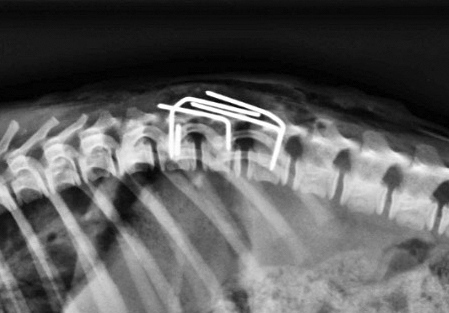

Las radiografías indicaban la fractura de su vértebra torácica T13, ( la que articula con su última costilla), con un desplazamiento importante que comprometía el canal medular dorsoventral, en el cuerpo de Malta.

En este caso, el profesional eligió la fijación con clavijas y PMM (Polimetil metacrilato) y enclavijamiento de titanium, con la asistencia y la responsabilidad de la anestesia del veterinario Jorge Pablo Vaccari.

“La dificultad de esta técnica se presenta en pacientes de tamaño pequeño debido a huesos diminutos”, comentó el cirujano, por lo que se requiere de mucha concentración y precisión.